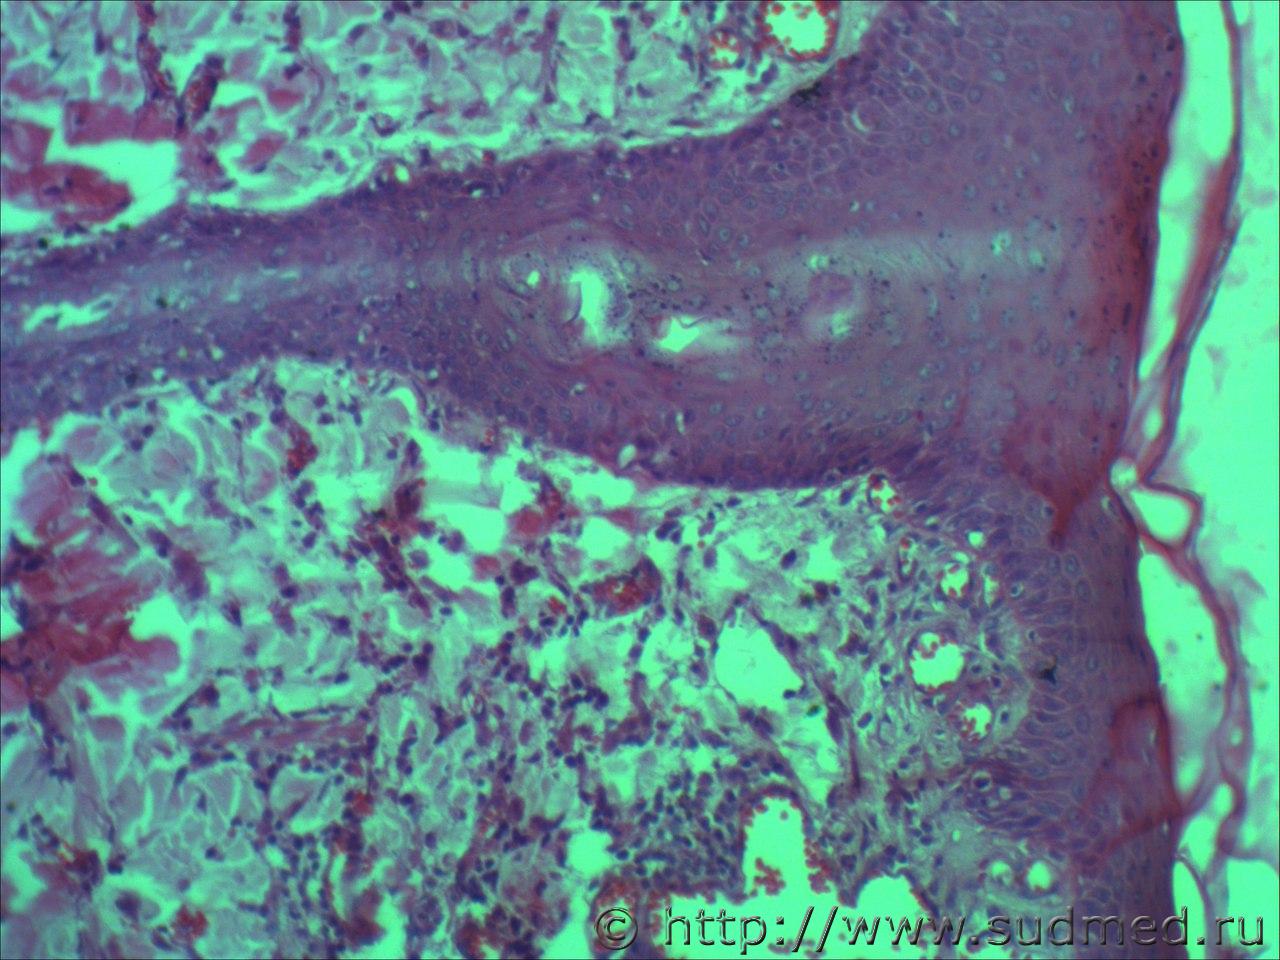

вижу что тяжи клеток эпидермиса проникающие в глубокие слои кожи и подлежащие ткани. Размеры клеток варьируют, слабовыраженное ороговение отдельных клеток, обильный воспалительный инфильтрат, пласты эпителиальных клеток в виде гнезд отделяются от эпидермиса. Склонен к ПКР

круглоклеточная опухоль, эпителий без патология

Фото низкого качества.

Попробую предположить,что на фото плазмоцитома и псевдокарциноматозная гиперплазия.